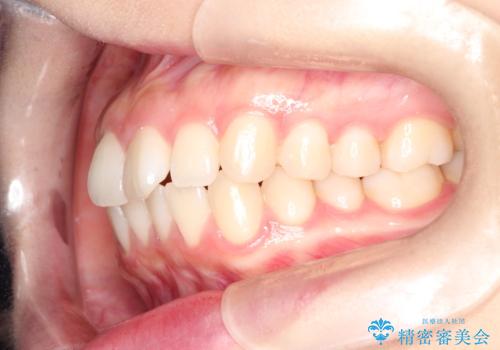

前歯のがたつきをインビザラインで目立たない矯正

- 上下の前歯のがたつきを主訴に来院されました。

マウスピースでの矯正を希望されたので、インビザラインで矯正治療を行うこととしました。

インビザラインではシュミレーションによりどのように歯が動くかを確認して矯正することができるので、患者様も安心して矯正をすることができました。